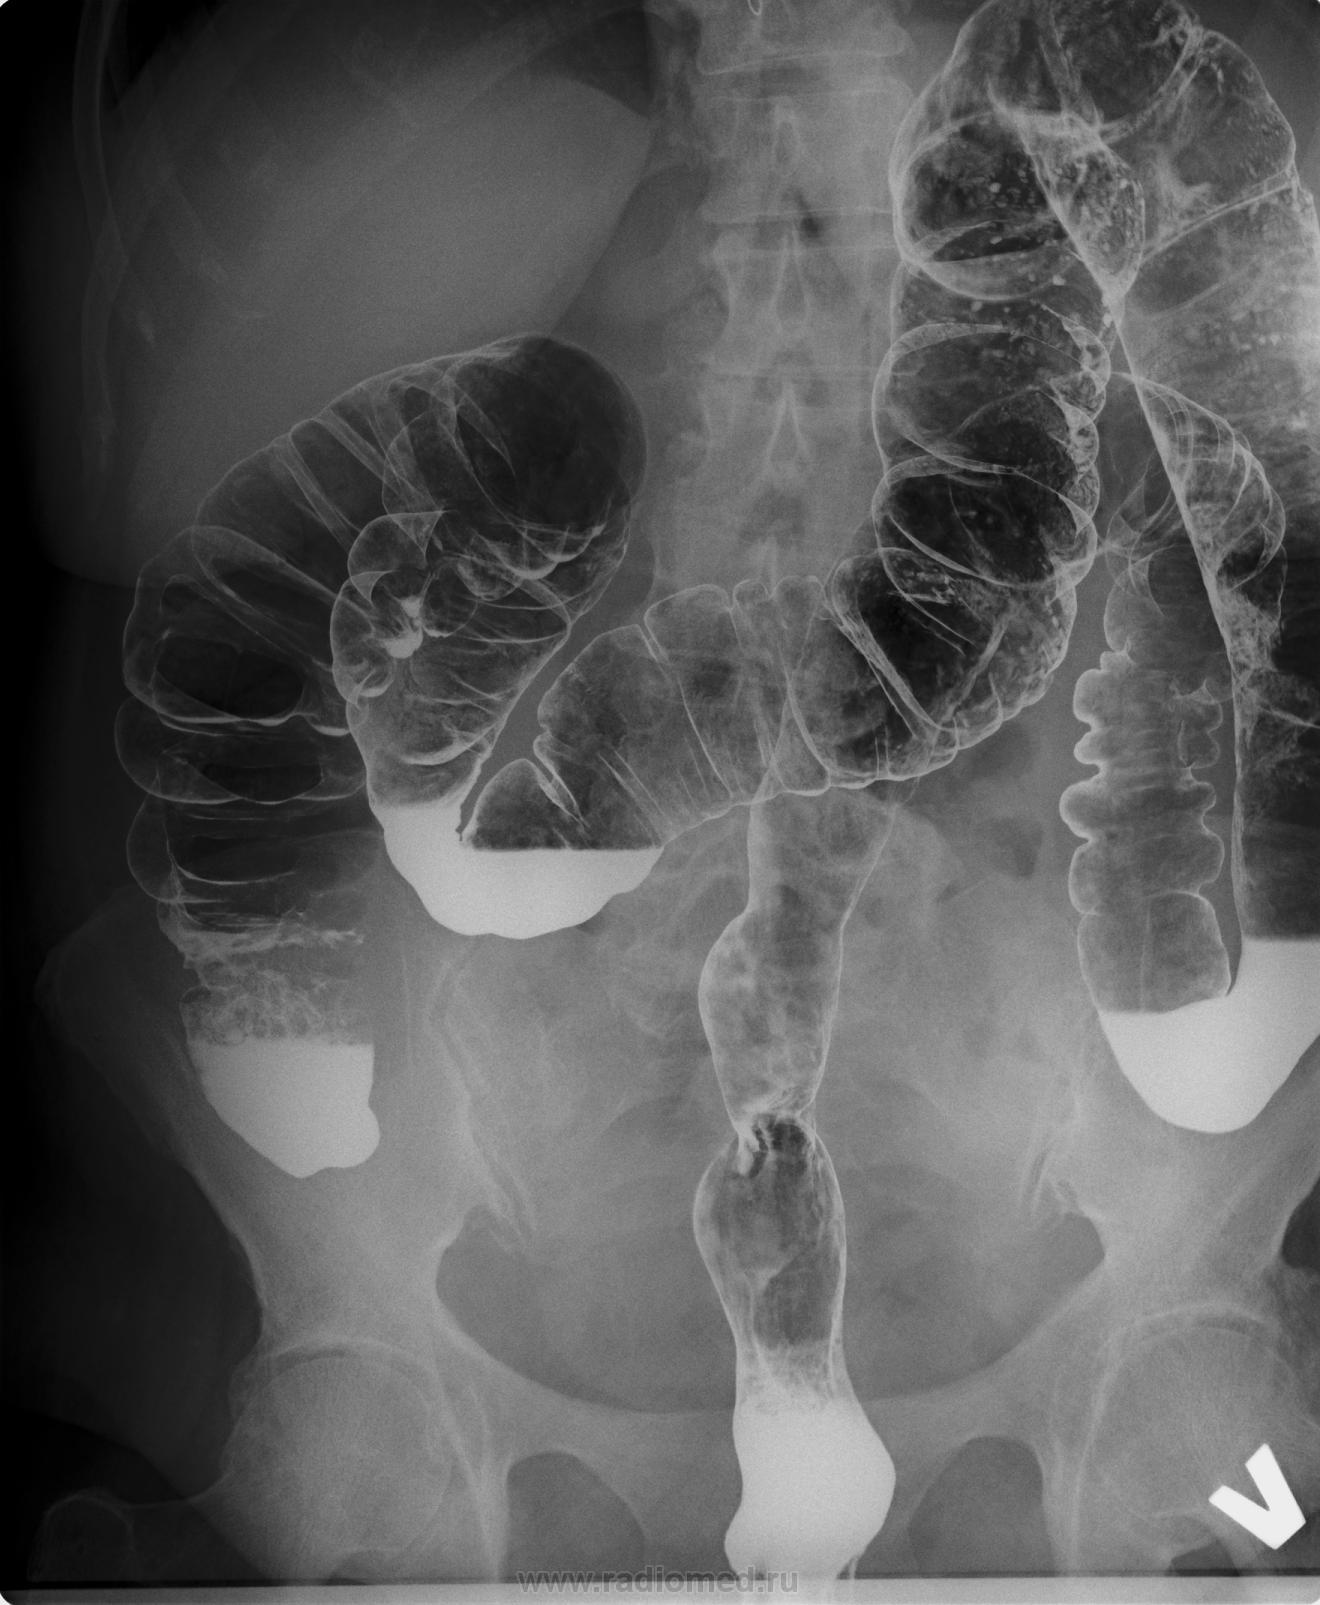

Слепая  после дефекации расправилась. Помогите оценить состояние слизистой ректосигмоидного отдела.

Ректо-сигмоидный угол оценивается на снимке в боковой проекции. Он у вас второй. Ничего особенного.

+1. ИМХО:  если речь идёт о оценке рельефа слизистой, то при  той методике котрую вы использовали ( первичного двойного контрастирования), сделать это не представляется возможным, так стенки кишки расправлены газом  и нормальных складок слизистой мы не можем увидеть.

ИМХО:потому, что при раздувании газом нормальные складки раправятся (что мы и видим в данном наблюдении), но рельефа складок слизистой мы не можем увидеть,т.к.складок в данной ситуации нет как таковых, в силу того , что они расправлены воздухом.

Имеет место быть недопонимание. На мой взгляд. Складки оценить при тугом заполнении не получится, а при двойном контрастировании их не только нужно, но и возможно оценивать. Кишка расправляется воздухом или водой, не раздуваясь при этом)), - складки становятся различимы (одна от другой). Главное, различить патологию слизистой - а она будет заметна и на пневморельефе - либо контраст импрегнирует, либо пятнит, либо стенку кишки деформирует, проникает если глубже в слои.

Уважаемый Виктор Григорьевич, вы делали всё правильно! Я хотел только сказать, что при использовании методики первичного двойного контрастирования, не представляется возможным оценивать СКЛАДКИ слизистой, так как их(складок) как таковых не может быть, в силу того что стенки кишки расправлены( раздуты газом).  Иными словами, складки слизистой видны только тогда когда стенка  кишки не растянута.

Андрей Юрьевич, я не имел ввиду таниновый рельеф и ирригоскопии с танином мы не делаем уже лет 20. Да и зачем? Для оцеки состояния слизистой толстой кишки есть колоноскопия.

На мой взгляд, патология очевидна, экзофитное образование сигмовидной кишки (полип?), гистологически - аденокарцинома. Не думаю, что это образование столь же четко опредедялось на рельефе.